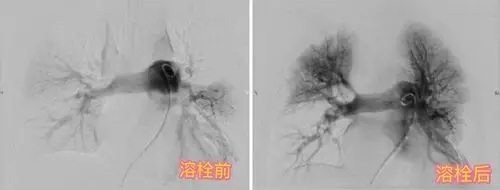

肺栓塞的影像诊断与鉴别诊断